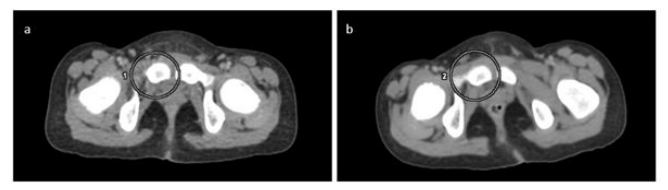

We encountered an artifact on the thoracic and abdominal region of Trans axial computed tomography (CT) images in the PET-CT (Positron emission computed tomography) scan of each patient throughout the day. Which were showed near spiral streaks across Tran's axial images.

The streak artifact is software or reconstruction-based artifact caused due to CT acquisition parameters mismatch. We describe a rare cause of the streak artifact that appeared on a Tran's axial CT image because of change in CT parameters like scan type, rotation time, recon recon type, pitch, noise index and all.

Our department has a positron emission comput- ed tomography (PET-CT) scanner (Mcxåel discovery IQ 5 ring, s/n We encountered an artifact on the thoracic and pelvic region of Tran's axial CT images in the PET-CT scan of each patient throughout the day. Which were showed near spiral streaks across Tran's axial images? On careful examination and in particular viewing CT images in IX)ne and abdominal window, it became ap- parent that the streaks in the Trans axial slices were spiral at thoracic and pelvic region. The remaining slices did not show this kind of artifacts. The artifact persistent on the CI' scan even after cleaning of the mylor window with warm wa- ter or disinfect solution. We felt that the possible reason for the artifact could due to defect in the collimation of X- rays.

We immediately made a call to service engineer and find insufficient dialectical oil [Figure and while opening CT gantry for filling the dielectric oil to the CT tubes he found breakdown at the HV cathode cable (Figure ICI. Immediately placed an order for the spare part and re- placed it on an emergency basis. After that service engineer done all CT QA and QC calibration procedures but later we again found the same artifacts on the CT Trans axial images of all and PET-CT scan-based patients. Then GE engineer suspected on the CT acquisition, reconstruction meth- ods and we decided to review the CT parameters like scan type, rotation time, recon mode, recon type, pitch, noise index and all. Our review revealed difference in CT reconstruction type and rotation time.

In the earlier protocol the standard recon type and rotation time was 0.6sec with standard recon mode which was now changed to soft recon type, IQ enhance recon mode with rotation time of 0.7sec.